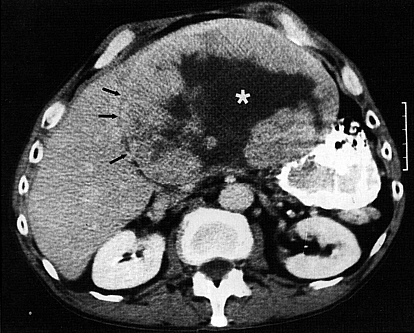

Em geral, a ultrassonografia ajuda, mas a tomografia computadorizada (TC) e a ressonância magnética (RM) do fígado são mais precisas na detecção do câncer.

No fígado, as lesões tendem a ser maiores e múltiplas. Muitas vezes os sintomas iniciais podem ser os mesmos de uma cirrose hepática severa.